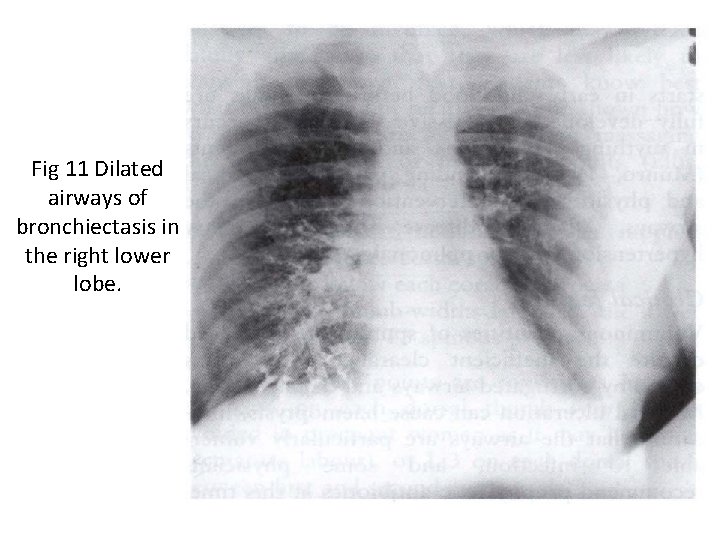

Investigations • Bacteriological and mycological examination of sputum • In addition to common respiratory pathogens, sputum culture may reveal Pseudomonas aeruginosa, fungi such as Aspergillus and various Mycobacteria. • Frequent cultures are necessary to ensure appropriate treatment of resistant organisms. • Radiological examination Bronchiectasis, unless very gross, is not usually apparent on a chest X-ray. • In advanced disease, thickened airway walls, cystic bronchiectatic spaces, and associated areas of pneumonic consolidation or collapse may be visible. • CT scan of chest is much more sensitive, and shows thickened dilated airways

Fig 11 Dilated airways of bronchiectasis in the right lower lobe.